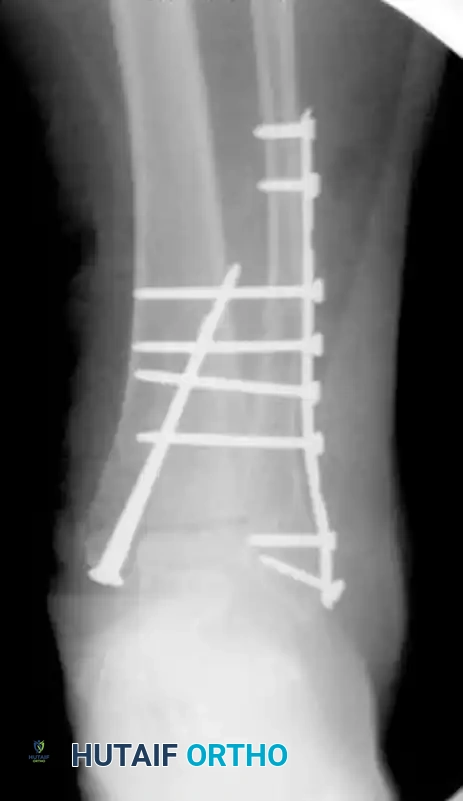

Following meticulous surgical débridement of the open wound, the fracture must be definitively treated with internal fixation. Because of the patient’s profoundly poor bone quality, standard fixation is inadequate. To achieve the necessary stability, the construct is augmented. Multiple transfibular/transtibial screws are utilized to significantly increase fixation purchase, locking the fibula to the tibia and effectively neutralizing the syndesmosis and the distal tibiofibular articulation.

Postoperative radiograph illustrating definitive internal fixation. Note the use of multiple long transfibular/transtibial screws traversing the syndesmosis to maximize cortical purchase in osteoporotic bone.